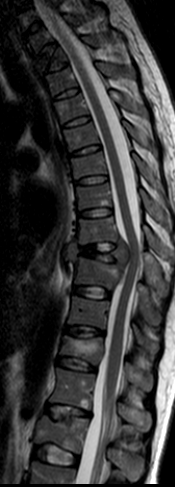

Вот МРТ картина:

Коллеги, а какой аномалии может идти речь??? На МРТ все признаки поражения костного мозга тел и ножек позвонков, инфильтрация с снижением сигнала на Т1, эти изменения видны на нескольких уровнях. Ищите онкологию (лимфому например) или патологию крови. А натечника никакого нет; сдавление спинного мозга значительное.

Я не специалист по МРТ, но на снимках отчетливо видна "+ткань" на уровне деструкции Th9-10 с компрессией спинного мозга. На мой взгляд, разница структуры позвонков отмеченых желтыми и красными стрелками - не норма, кроме того, хотелось бы узнать, если здесь есть, у специалистов МРТ, чем можно объяснить то, что я отметила синими стрелками.

Я считаю, что в данном случае имеют место множественные очаги остеолитической деструкции, которые ничем другим кроме опухоли (первичной или мтс) объяснить нельзя